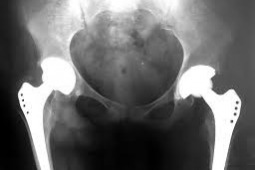

- To właśnie ze względu na ograniczony dostęp do pomocy ortopedycznej powstała inicjatywa Minister Zdrowia. Profesor Zembala zagwarantował wykonanie dodatkowych wszczepień endoprotez - powiedział w rozmowie z dziennikarzem "Menedżera Zdrowia", profesor Paweł Małdyk, konsultant krajowy w dziedzinie ortopedii i traumatologii narządu ruchu.

Jak wyjaśnił konsultant krajowy, zapowiedziane operacje zaczną być wykonane już w październiku. - Trzy tysiące osób w skali kraju, jeszcze w tym roku otrzyma pomoc - powiedział prof. Paweł Małdyk.